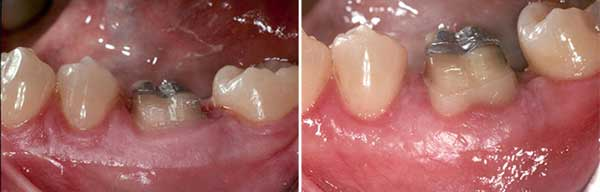

6. Recommandez-vous l’allongement de la couronne avant ou après un traitement de canal, et pourquoi ?

À mon avis, l’allongement de la couronne devrait être fait après le traitement de canal. Il y a plusieurs raisons à cela. L’une d’elles est que, dans la plupart des cas, le traitement de canal détermine la possibilité ultime de sauver la dent et si une restauration appropriée peut être placée sans compromettre l’intégrité de la dent. La deuxième raison est la facilité du traitement. Une fois l’allongement de la couronne effectué, en raison de la nature du traitement et de l’importance de l’implication des tissus durs et mous, il faut jusqu’à 10 semaines pour obtenir une cicatrisation idéale avant de pouvoir appliquer à la dent ou aux structures environnantes toute contrainte supplémentaire, telle que la pose d’une digue en caoutchouc sur la dent ou le fait de demander au patient d’étirer ses joues pendant de longues périodes. Ce type de retard dans le traitement de canal d’une dent compromise peut potentiellement conduire à une défaillance complète de la dent et à un traumatisme supplémentaire dû à l’invasion bactérienne ou à la destruction de la structure de la dent sous l’effet de l’usure normale. Un autre facteur à prendre en compte est qu’en effectuant le traitement de canal après l’allongement de la couronne, les fibres de Sharpey nouvellement formées et l’attache du tissu conjonctif peuvent être soumises à un stress énorme par le clamp de la digue en caoutchouc, en particulier dans les situations où il n’y a pas de dent distale adjacente à utiliser comme ancrage du clamp. Ce type de stress peut conduire à des dommages supplémentaires du ligament parodontal (PDL) et des tissus conjonctifs nouvellement formés. (figure 3)

Figure 3